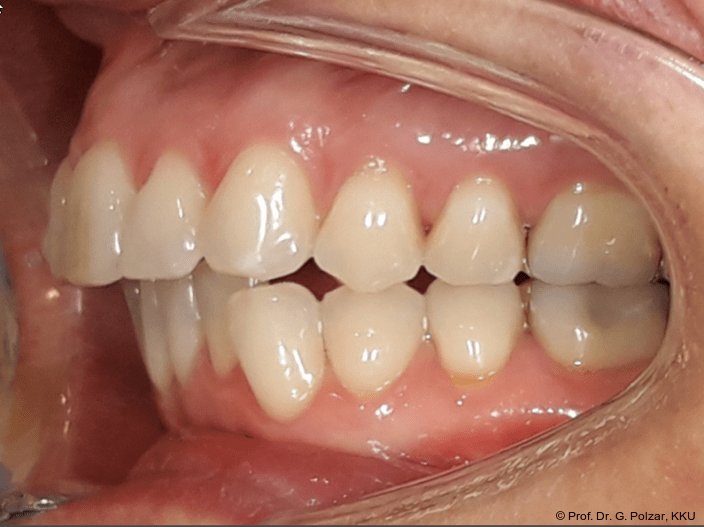

Die 38-jährige Patientin stellte sich 2019 zum ersten Mal in der Praxis vor. Nach einer drei­jährigen kieferorthopädischen Behandlung im Jugendalter mit Multibandapparaturen kam es im Laufe der Zeit zu einem Rezidiv mit Retro­inklination der oberen mittleren Frontzähne. Der Wunsch der Patientin war es, „wieder gerade Zähne“ zu haben. Die sehr gesundheitsbewusste Patientin hatte sich im Vorfeld von 14 kieferorthopädisch tätigen Kollegen beraten lassen, war aber von den vorgeschlagenen Therapiemaßnahmen nicht überzeugt (Abb. 1a–d).

Der intraorale Befund zeigte eine scheinbar neutrale Verzahnung. Trotz Lingualretainer in der UK-Front war ein Engstand in der Unterkieferfront mit leichter Protrusion erkennbar. Appro­ximal des Zahnes 41 waren deutliche schwarze Dreiecke zu erkennen, zudem wies der Zahn eine leichte gingivale Rezession auf (Abb. 3a–f).